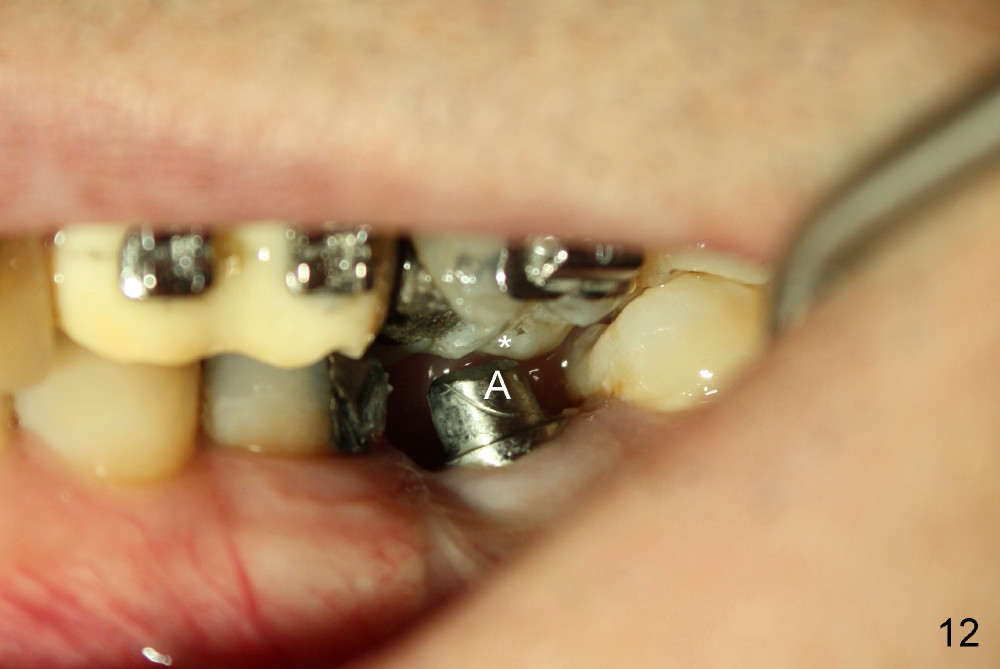

A 51-year-old man needs implants at the sites of #12,13,19 (Fig.1). The teeth #12 and 13 are extracted. An implant is placed at #19 (Fig.2 <). After osteointegration, an abutment is placed (Fig.2 A). The opposing tooth, #14, is found supraerupted. Two mini-implants are placed at the mesiobuccal and distolingual areas of #14 (Fig.3 (mirror view) <) and a power chain (*) is placed for intrusion. In the next 8 months, these 2 mini-implants become loose. Two new mini-implants are placed in the mesiolingual and distobuccal regions (Fig.4 ^). The one in the distobuccal region is loose after a while (Fig.6,7 >). In brief, mini-implants are not efficient in intrusion. At this time, the implants at the sites of #12,13 apparently osteointegrate (3 months post placement) and abutments are placed (Fig.4). Provisional crowns are fabricated (Fig.5). Brackets are placed between #11 and 15 with the bracket at #14 placed more coronally than those of the neighboring teeth (Fig.6-8). Mesially there are two excellent anchorages (#12,13) as well as the mesiolingual mini-implant. The distal anchorage is #15. In the next 5.5 months, the tooth #14 is intruded (Fig.9,10), but the 2nd molar is mobile (not as strong as #14). A longer mini-implant is placed in the distobuccal corner (>, more apical than before (Fig.7)). The distobuccal mini-implant is found to be mobile in 3 weeks (Fig.11). It appears that there is enough clearance for restoration of #19 (Fig.12). Power chains are placed between the mesiolingual mini-implant and #14 buccal tube until the appointment for crown prep. In this way, the lingual cusps may ascend (Fig.13 red arrow), while the buccal ones may descend (black arrow). The occlusal clearance will be more favorable.